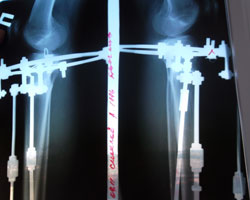

Рентгены перед снятием аппаратов.Для минимума следов от операции Н.Н. фиксировал кольцо всего двумя тонюсенькими спицами.